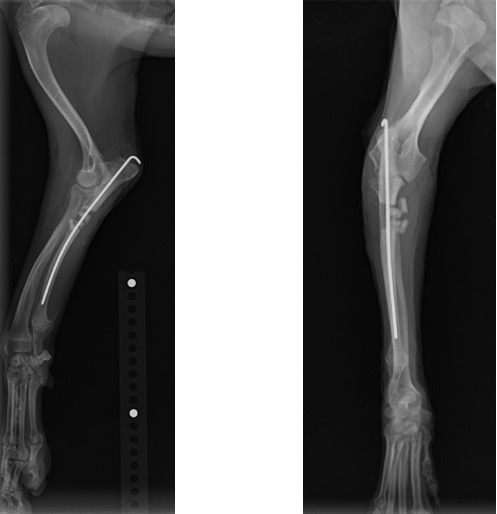

術後の側面像と頭尾側像 (骨切り後に尺骨のアラインメントを合わせるために髄内ピンとして1.2mm K-wireを刺入しました)

術後の側面像と頭尾側像 (前例と同じく髄内ピンとしてK-wireを刺入したのちに切り取った骨片を破砕し、骨切部分へ再移植しました。)